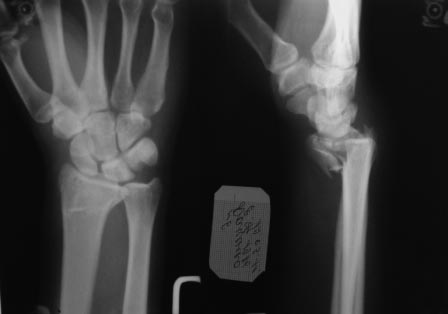

Нет не в вывихе, т. К. Из-за спицы проведенной через обе кости предплечья, то ротационные движения и подвижность локтевой кости резко ограничены, это может в некоторых проекциях расцениваться как подвывих, если найду покажу финальный снимок, там все рентгенологические показатели восстановлены.